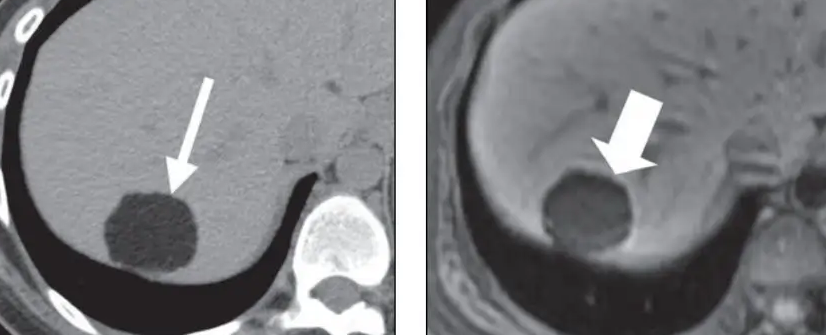

第三个,我们还可以通过一些影像学的造影技术,看看这个结节里面,是静脉供血还是动脉供血;

第四个,我们还可以通过一些血清标记物的检测,比如说甲胎蛋白、癌胚抗原、异常凝血酶原时间等等,这些癌性指标的检测,可以提前预测,看看结节是良性的还是恶性的,早点加以区别。

良性结节和恶性结节的治疗是不一样的,虽然检测有一定难度,但是我们的检测手段还在不断提高,所以说这样的病人,基本上还是可以在早期得到及时的诊断。